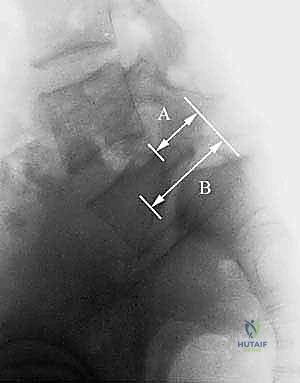

نظام تصنيف مايردينغ (Meyerding Classification)

لتقييم مدى خطورة الانزلاق الفقاري وتحديد خطة العلاج المناسبة، يستخدم الأطباء، وعلى رأسهم الأستاذ الدكتور محمد هطيف، نظام تصنيف يُعرف باسم "تصنيف مايردينغ". يقيس هذا النظام نسبة انزلاق الفقرة العلوية بالنسبة للفقرة السفلية:

- الدرجة الأولى (Grade I): انزلاق بنسبة 0% إلى 25%. (غالباً ما تُعالج تحفظياً).

- الدرجة الثانية (Grade II): انزلاق بنسبة 26% إلى 50%.

- الدرجة الثالثة (Grade III): انزلاق بنسبة 51% إلى 75%. (غالباً ما تتطلب تدخلاً جراحياً).

- الدرجة الرابعة (Grade IV): انزلاق بنسبة 76% إلى 100%.

- الدرجة الخامسة (Grade V أو Spondyloptosis): انزلاق كامل للفقرة لتسقط تماماً أمام الفقرة التي تحتها، وهي حالة شديدة التعقيد تتطلب مهارة جراحية فائقة.

هي الخطوة الأولى والأساسية. يتم التقاط صور للعمود الفقري من عدة زوايا (أمامية، جانبية، ومائلة). الأشعة الجانبية هي الأهم لتحديد درجة الانزلاق (حسب تصنيف مايردينغ). كما يتم إجراء أشعة ديناميكية (أثناء الانحناء للأمام وللخلف) لتقييم مدى "عدم الاستقرار" (Instability) وحركة الفقرة أثناء الحركة. -